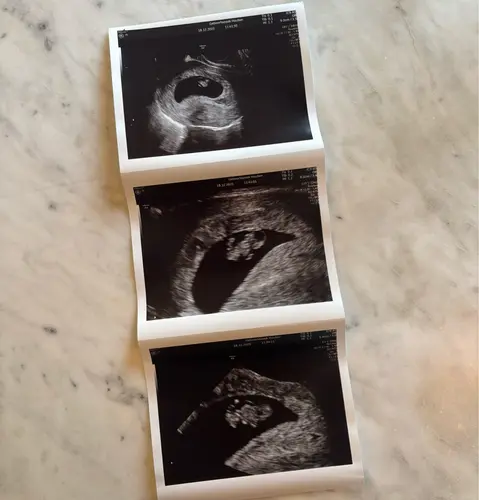

Nu 9+1, nog steeds alles helemaal in orde met allebei 😍🙏🏼🙏🏼

Begin er iets meer vertrouwen in te krijgen 🤞🏼♥️